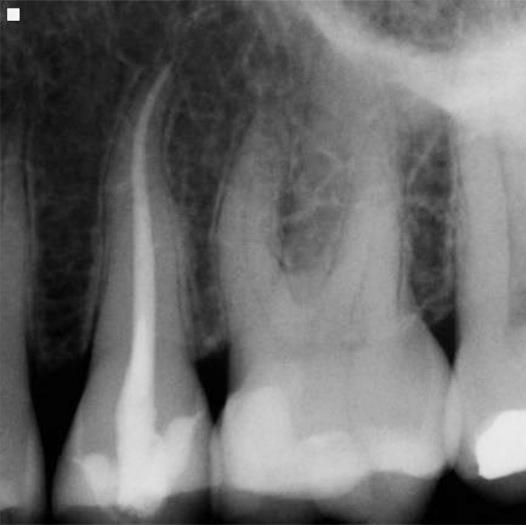

After

After Root Canal treatment